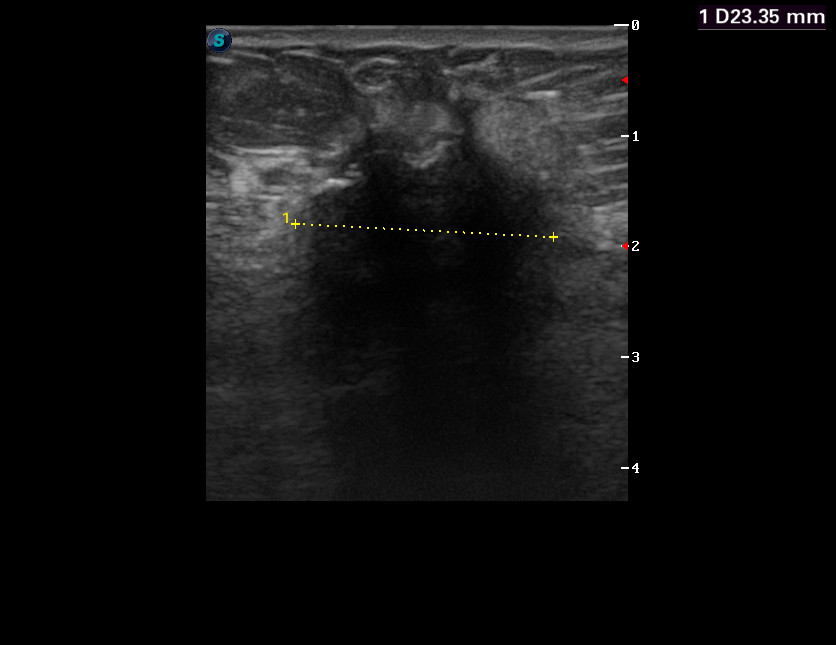

Бабушка 1936 г, правый сосок втянут

Похоже что есть?

А что там в подмышечной впадине? Но очень похоже... и должно определяться пальпаторно,судя по размерам.

Да, пальпаторно есть.zubr писал(а):А что там в подмышечной впадине? Но очень похоже... и должно определяться пальпаторно,судя по размерам.

Бабушку отправили к онкологам.